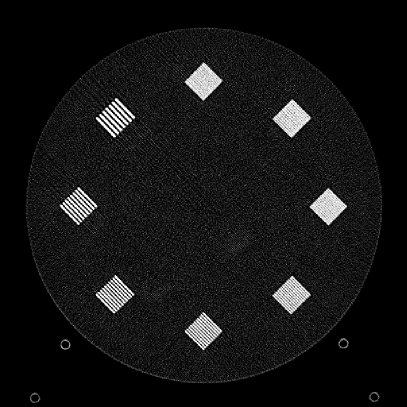

Figure 10: Clinical Standard hybrid IR vs JENG performance, with a display window center of 650 HU and a window width of 1500 HU. The spatial frequencies for bar patterns from top going clock-wise are 1.2, 1.0, 0.9, 0.8, 0.7, 0.6, 0.5, 0.4 mm-1. (a) The clinical Standard hybrid IR at L1 denoising strength using a soft tissue high contrast kernel. Note that significant aliasing streaking artifacts are present near the bar patterns. (b) JENG at a comparable L1 noise level but with much clearer bar pattern and fewer artifacts than the clinical standard hybrid IR. (c) The clinical standard hybrid IR at a stronger denoising strength of L3. (d) JENG at a comparable L3 noise level.

The first experiment we performed was a visual comparison of in-plane spatial resolution between JENG and the clinical standard hybrid IR. We used the ACR phantom module 4 for this evaluation, which has 8 resolution bars of various spatial frequencies from 0.4 mm-1 to 1.2 mm-1. To obtain a fair comparison, we matched the image noise variance in the uniform regions of JENG and the clinical standard hybrid IR and studied their in-plane spatial resolution and undersampling streaking artifacts. In addition, we performed two sets of experiments. The first set of experiments matched their image noise variance at the L1 denoising strength of the clinical standard method with a noise variance of 33926 in the uniform regions. The second set of experiments matched their image noise variance at stronger L3 denoising strength of the clinical standard method with a noise variance of 12988 in the uniform regions.

Fig. 10 is an example image for resolution bars and the spatial frequencies for the bar patterns from top going clockwise are 1.2, 1.0, 0.9, 0.8, 0.7, 0.6, 0.5 and 0.4 mm-1. Fig. 10(a) is the resolution bars reconstructed by the clinical standard hybrid IR at L1 denoising strength. Fig. 10(b) is JENG reconstructed at an image noise variance comparable to the L1 denoising. Fig. 10(c) is the clinical standard hybrid IR at a stronger L3 denoising strength and we can observe that the result at L3 denoising leads to less image noise than the result at L1 denoising in Fig. 10(a). Fig. 10(d) is JENG at an image noise variance comparable to the L3 denoising. To help readers better see the image quality difference between the clinical standard hybrid IR and JENG, Fig. 11 is the difference image between the two algorithms at L1 denoising. A noticeable difference between the clinical standard hybrid IR and JENG is that the clinical standard method in Figs. 10(a) and (c) have strong undersampling aliasing artifacts near the phantom periphery, which show a pattern of high density streakings and the streakings point along the direction of X-rays. In addition, the magnified sub-figures show that the bar pattern at 0.8 cycles/mm is unresolved with blurry details. In contrast, JENG in Figs. 10(b) and (d) effectively decimates the undersampling artifacts and the bar pattern in the magnified sub-figures of JENG is completely resolved with clearer details.

For the clinical standard hybrid IR, a possible cause for its loss of image resolution and the presence of aliasing artifacts in the image periphery can be explained by the Nyquist-Shannon sampling theorem. Nyquist-Shannon sampling theorem concludes that the discrete projection sampling rate for an application that requires Fourier Transform and data interpolation must be sufficiently high to avoid alias in the frequency domain and capture all the needed information in the continuous image domain. Given that the clinical standard hybrid IR involves Fourier Transform and data interpolation operations, the low projection sampling rate at a high helical pitch of 2.8 might lead to aliasing artifacts and a loss of spatial resolution for the clinical standard method. In contrast, JENG has no Fourier Transform or data interpolation operations and is completely based on linear algebra and acquisition physics modeling. Therefore, JENG is not limited by Shannon-Nyquist Theorem and its images are less susceptible to aliasing artifacts and show clearer bar patterns.